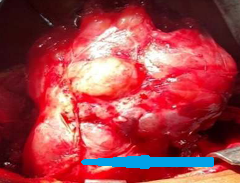

Χειρουργικά παρασκευάσματα εξαιρεθέντων ενδομητριωμάτων (Ευγενική παραχώρηση Dr. V. Penopoulos)